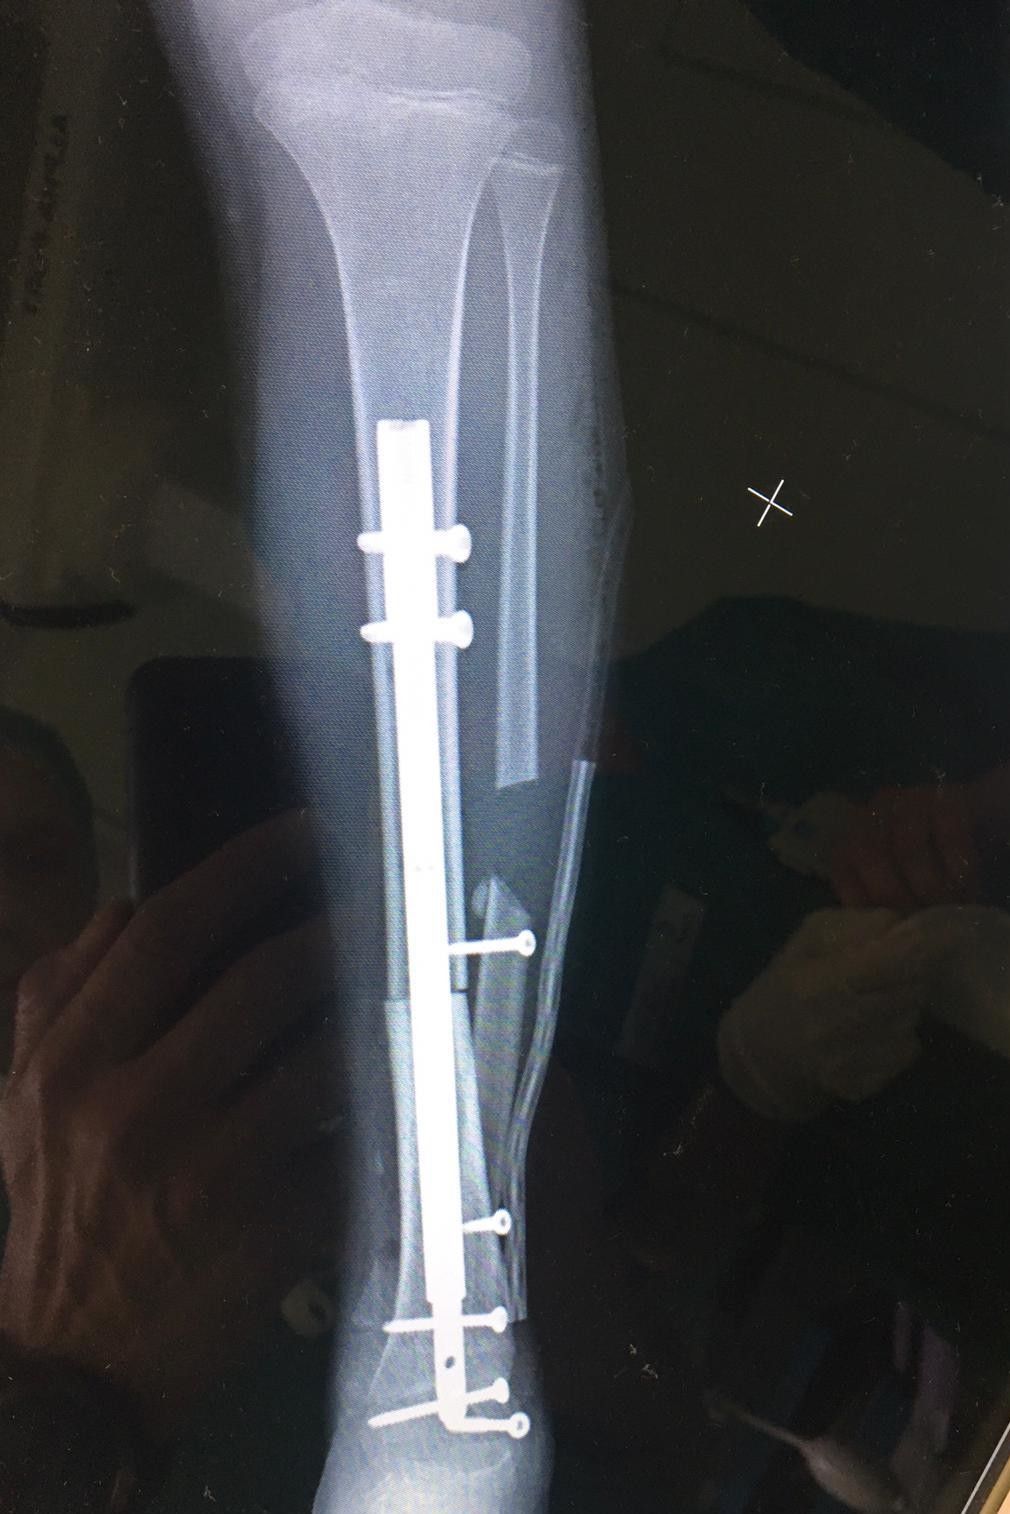

La bimba, dopo la diagnosi, è stata seguita presso il reparto di Oncoematologia pediatrica dell’ospedale Regina Margherita diretto dalla professoressa Franca Fagioli, dove ha eseguito la chemioterapia, e nei giorni scorsi è stata sottoposta all’intervento di asportazione del tumore e salvataggio della caviglia con ricostruzione con osso omoplastico da donatore e sintesi con un chiodo allungabile.

La tecnica eseguita - informa l'istituto Rizzoli - rappresenta una assoluta novità in quanto il chiodo inserito per stabilizzare l’impianto permetterà nei prossimi anni anche la regolare crescita dell’arto permettendo l’allungamento al termine della maturazione scheletrica. La chirurgia è stata pianificata nei minimi dettagli dalle due équipe di medici e ingegneri nelle settimane precedenti l’intervento. Nonostante la pandemia da COVID19, spiega ancora il Rizzoli, le cure legate a questo tipo di patologie si sono svolte regolarmente e senza ritardi pur attuandosi tra enti di regioni diverse. La bimba ora sta bene ed è appena stata dimessa.

"Il 'gioco' - conclude Manfrini - è stato usare il chiodo, un sistema presente sul mercato solo da pochi anni , fin dall'inizio: impiantare fin da subito il mezzo che servirà per 'allungare' la bimba nel modo meno traumatico possibile appena mostrerà lo sviluppo".

Le strategie chirurgiche disponibili sono oggi molteplici, comprendono pianificazioni virtuali della resezione ossea e ricostruzione mediante impianti protesici espandibili, protesi costruite su misura (anche con stampanti 3D), innesti ossei omoplastici provenienti dalle Banche di Tessuto Muscoloscheletrico e trapianti di osso autoplastico vascolarizzato, mezzi di sintesi originali.